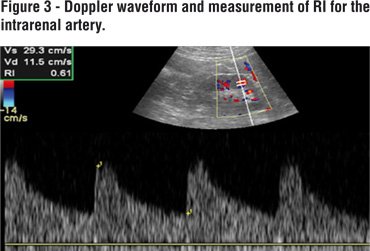

A systematic abdominal sonographic examination (4.5-5 MHz convex array transducer, Aloka alfa 6, Japan) was performed on all patients. The examination was performed with the subject in a supine and prone positions. Kidney measurements were obtained with the subject prone. Kidney length, width and thickness were measured using US. Kidney volume (total volume (Figure-1) and sinus volume (Figure-2)): lenght x thickness x width x 0.523 (5) were obtained. Parenchymal volume was calculated as total volume- sinus volume. RI was calculated automatically by Doppler US (Figure-3).

RI is a parameter which correlates with renal function, and it is logical that RI should increase when renal function decreases. Kidney volume and RI are predictors of renal function and correlate with body indexes (6). Mean RIs for left and right kidneys were 0.60 and 0.62, respectively, in our study. There was no significant correlation between total and parenchymal kidney volume and RI for either kidney (p<0.05).